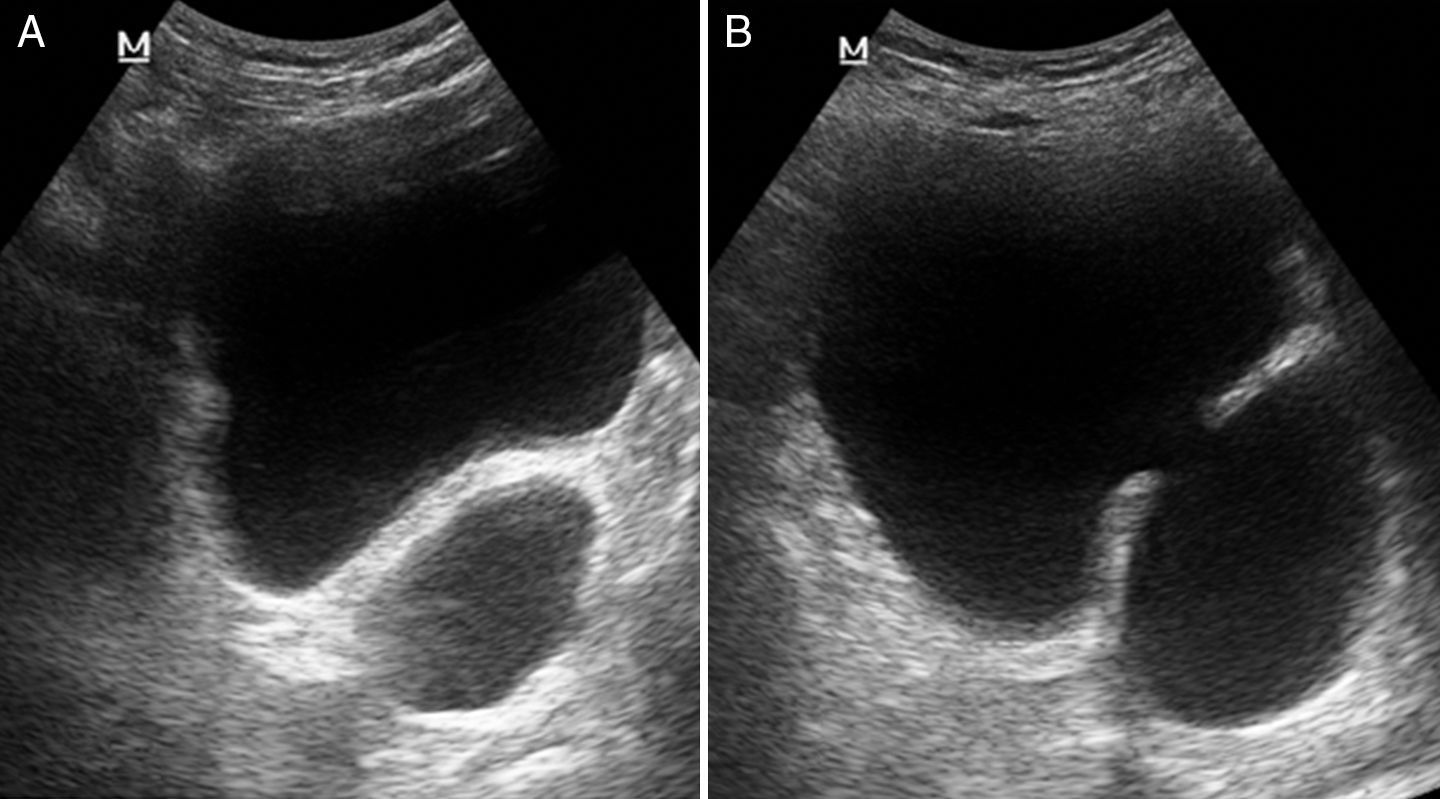

• Ultrasonido prostático: Medición exacta del volumen (normal menor a 30cc)